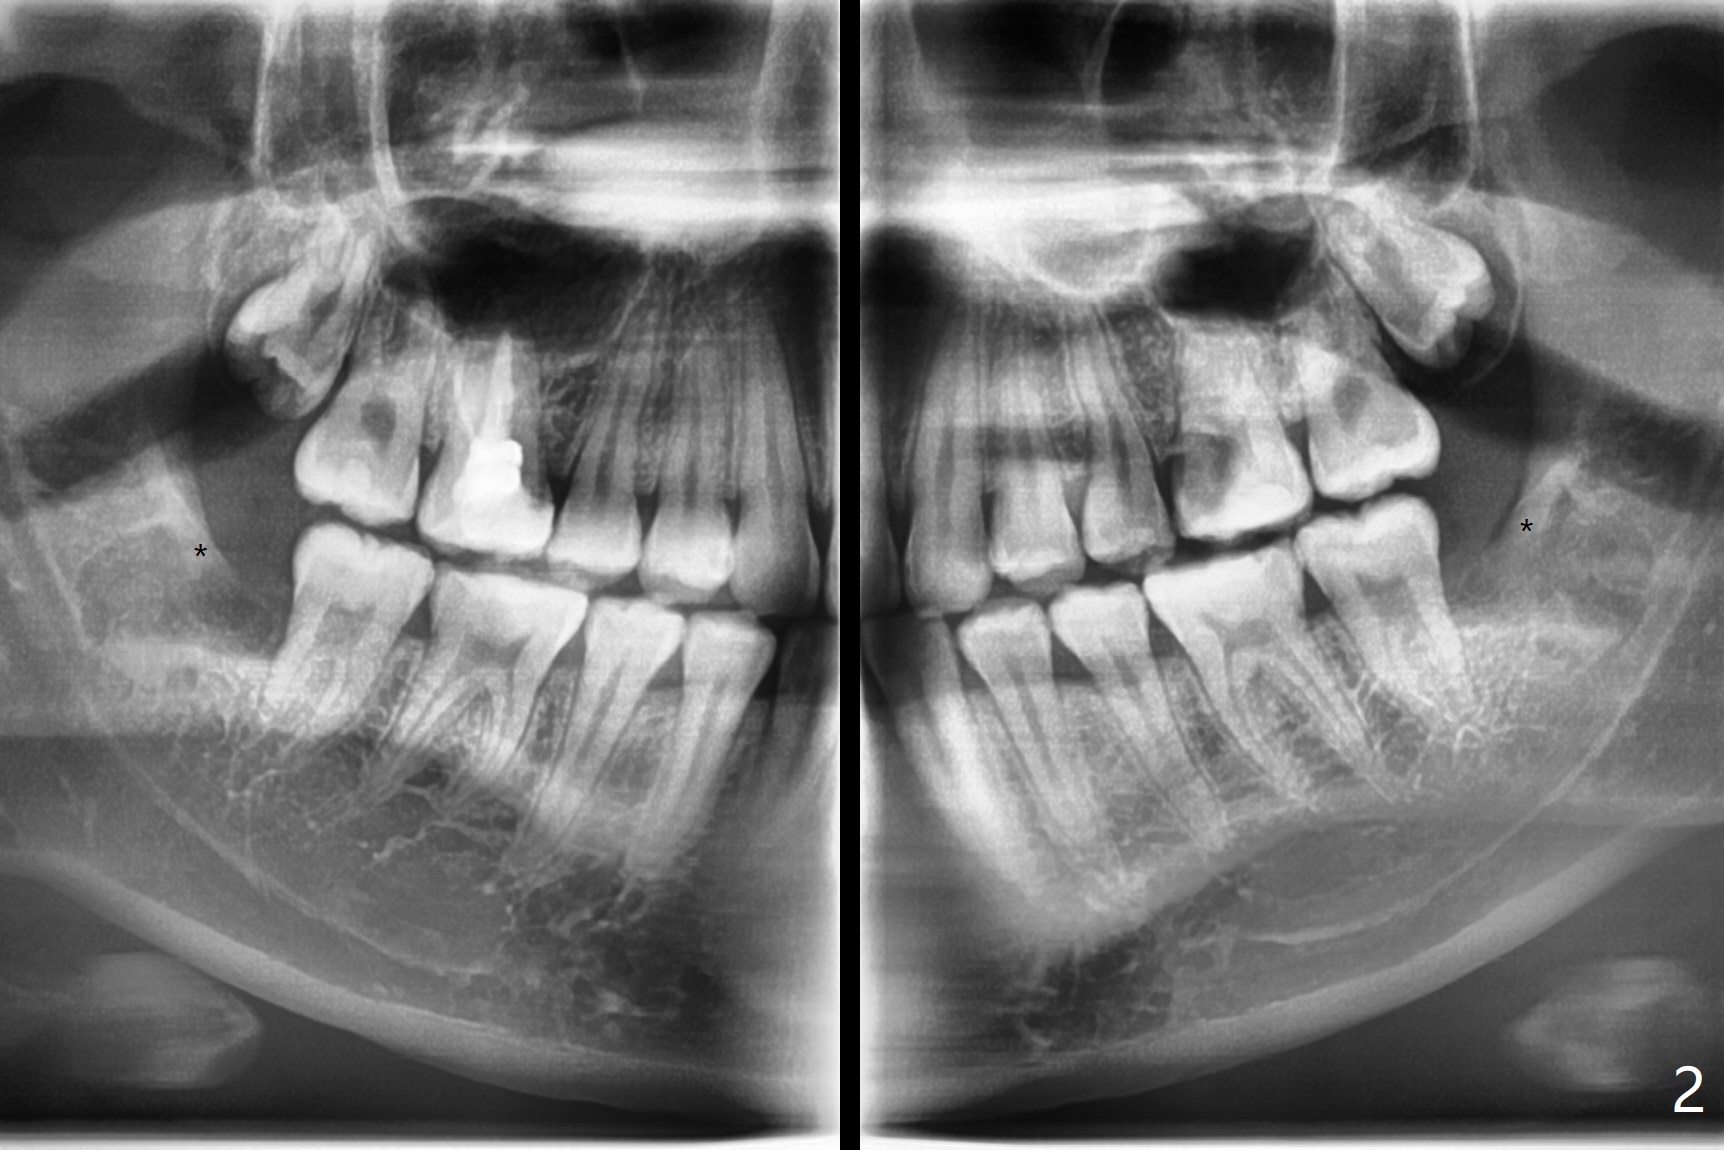

外斜嵴发育延申

20岁女由于右下智齿疼痛就诊,诊断后,要求先拔除两个下颌智齿。外斜嵴好像跨越牙槽窝远中(图一:*),拔除似乎没有缩短外斜嵴长度(图二:*),牙槽窝放置胶原塞。